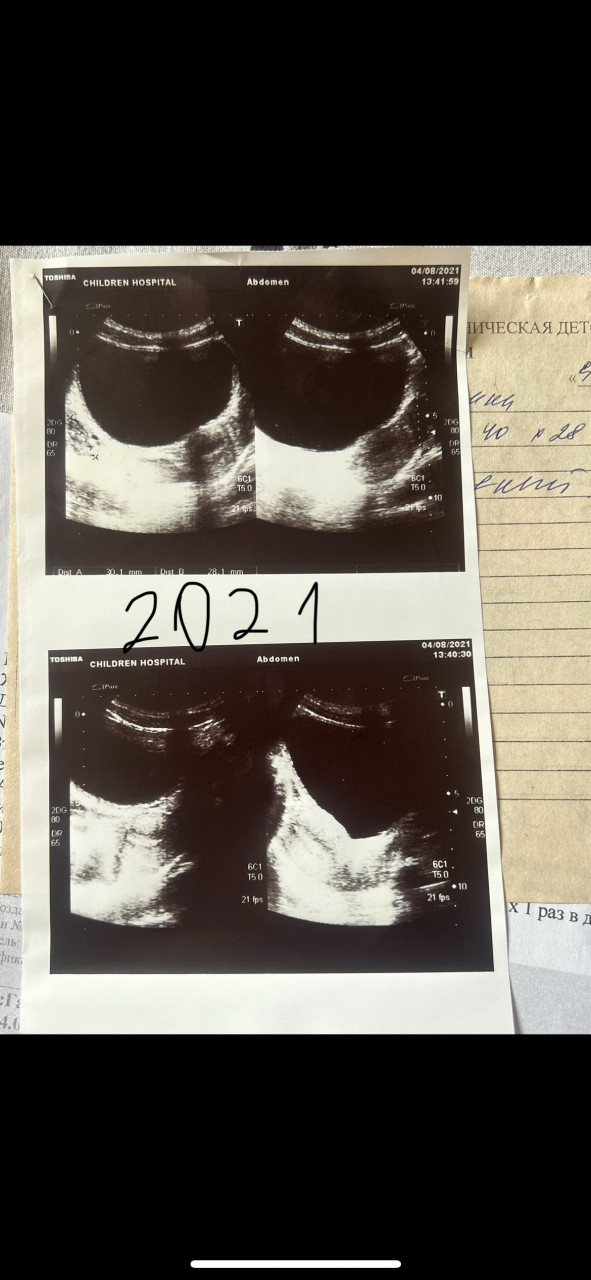

Здравствуйте, подскажите пожалуйста по моему вопросу. У меня очень болезненная менструация очень много крови со сгустками выходит цикл нерегулярный лет с 15 ходили по врачам делали узи ставили диагноз вторичная олигоменорея и вторичная дисменорея назначали циклодинон от которого толку 0 от боли так тоже ничего и не помогает назначали и пить до менструации обезболивающее за 5 дней до найз по 1 таб 2 раза в день и 3 дня менструаций, в первый особенно болезненный день свечи с индометацином больно невозможно как схватки потом в 17 лет поставили диагноз диффузно кистозная мастопатия в груди ощущаю комки грудь очень болит до месячных и во время них опять же назначали мастодинон который ничего не дал и обезболивающее вот и все пропила мастодинон 3 мес. В больнице врач узи начала говорить а кто вам такое в груди увидел хотя это она же и делала узи в первый раз я прикреплю ниже узи малого таза за 2021 и 2022 год давно подозревала у себя эндометриоз все симптомы подходят и вот вчера мама поехала на узи из-за кровотечения и ей поставили эндометриоз впервые за 40 лет в другой клинике заключение: Эхографические признаки гиперплазии эндометрия, умеренных диффузных изменений миометрия по типу эндометриоза, миомы тела матки небольших размеров, фолликулярной кисты правого яичника.  зашла сегодня ради интереса в чат джи пи ти и отправила ему свое узи он расшифровал мне его абсолютно по-другому за 2021 год вообще сказал что это узи мочевого пузыря я вообще в шоке а в узи за 2022 год нашлись действительно болезни а врач узи пишет что там все в норме кому верить уже не знаю( забыла указать длина цикла 32-51день, менструация длится 10 дней под конец совсем мазня и раньше бывало такое что между месячными была мазня в середине цикла сейчас во время овуляции болит левый яичник во время менструации боль отдает аж в ноги они будто отнимаются

Заключение УЗИ 2021 матка 40*28*46 мм эндометрий 5мм, однородный, миометрий не изменен, левый яичник 30*19*20, фолликулы до 5 мм в поле зрения 8-9 шт, правый яичник 28*16*17мм фолликулы до 7 мм, в поле зрения 7-8 шт. В дуглассовом пространстве жидкость -. УЗИ 2022 матка 41*30*48 мм, эндометрий 11мм, однородный, полость матки не расширена, миометрий однородный, шейка матки без особенностей, правый яичник 30*15*18 фолликулы до 13 мм в диаметре, 7-8 шт в поле зрения левый яичник 30*21*20 мм фолликулы до 6 мм в диаметре, 9-10 штук в поле зрения в дугласовом пространстве жидкость в небольшом количестве 5 мл.